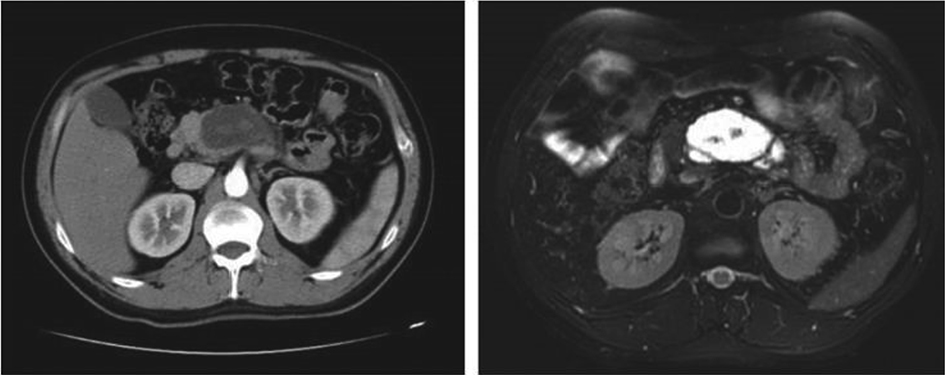

3. Development of the puncture channel. Over the past 10 years, endoscopic ultrasonography (EUS) has gradually become the third eye for endoscopists. Its combination with SMIS brings a new type model for the diagnosis and treatment of organic lesions outside the digestive tubes. For example, EUS-guided bile drainage (EUS–BD) and EUS-guided pancreatic duct drainage (EUS–PD) have been used as effective treatments after the failure of trans-nipple drainage; meanwhile the treatment strategy for acute necrotizing pancreatitis has also changed greatly. EUS-guided super minimally invasive drainage by gastric parietal puncture for pancreatic encapsulated necrosis and EUS-guided pancreatic cystic lesion puncture laurosinol ablation have become the mainstream treatment methods. In the future, SIMS operations like exploring and refining super minimally invasive drainage via a gastric puncture channel for suppurative cholecystitis, EUS-guided super minimally invasive gallstone extraction via a gastric puncture channel, EUS-guided portosystemic shunts and EUS-guided drainage of the chest, the abdomen and pelvic abscess, etc. will be the development directions.

FIG. 2.3 — SMIS through a puncture channel.